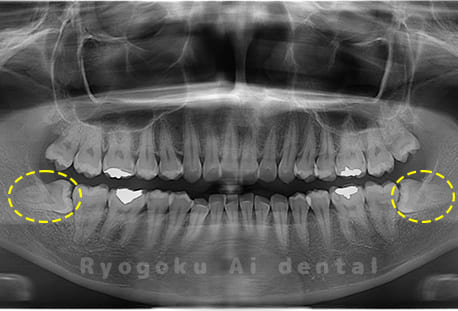

Case02

- 原因

- 下顎の水平埋伏智歯

- 治療内容

- 下顎の水平埋伏智歯を抜歯

<リスク・副作用>

手術後は痛み、腫れ、痺れなどの副作用が生じる場合があります。